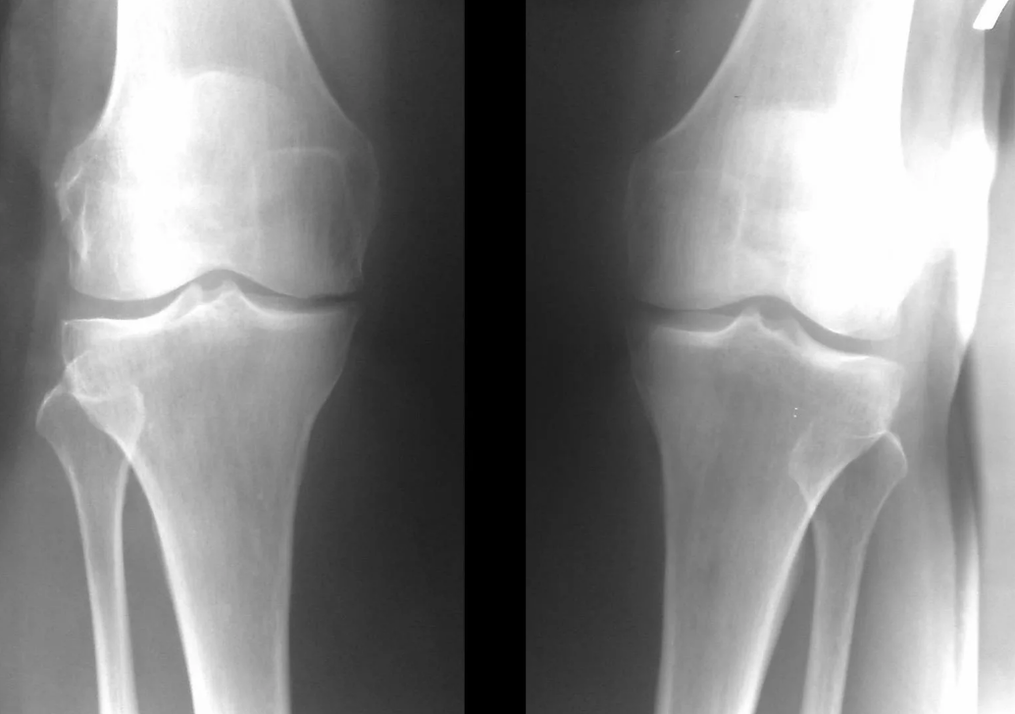

In den allermeisten Fällen reicht eine Untersuchung und Röntgenaufnahme des Kniegelenks in zwei Ansichten (direkt und seitlich) aus. Klinische Daten und Bildgebung helfen bei der Bestimmung des Krankheitsstadiums.

Im Frühstadium der Erkrankung mit geringfügigen Veränderungen des Knochengewebes ist eine Röntgenuntersuchung nicht so wertvoll. In diesem Stadium kann eine Gonarthrose durch eine Arthroskopie diagnostiziert werden. Die Präzision der Methode ist sehr hoch; Nur seine invasive Natur und sein Preis können es stoppen.

Ultraschall ermöglicht keine klare Visualisierung von Veränderungen des Gelenkknorpels und der intraartikulären Strukturen. Mit der MRT lassen sich Veränderungen der Knochen-, Knorpel- und Weichteilstrukturen des Gelenks sowie des subchondralen Knochens mit einer Genauigkeit von 85 % erkennen. Mithilfe der Szintigraphie kann die Stoffwechselaktivität des periartikulären Knochengewebes beurteilt werden.